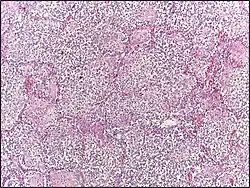

Dysgerminoma | Dysgerminoma characterized by uniform cells resembling primordial germ cells separated by fibrous septa with lymphocytes. | Category: Histopathology of ovarian dysgerminoma | Ovarian dysgerminoma |

![]() |